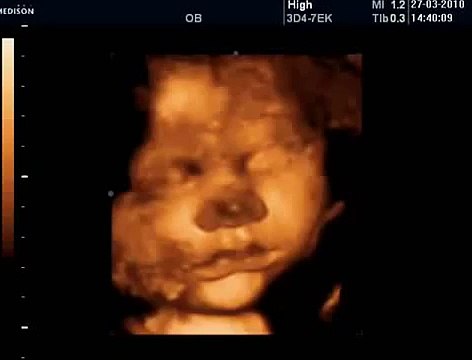

33 Haftalık Gebelik Bebek Ultrason Görüntüsü

Hafta hafta gebelik dönemi 33 haftalık bebek ultrason görüntüsü. Gebelikte 33. hafta daha çok bilgi için gebelikveannelik.com/33-hafta-gebelik sayfamızı ziyaret edebilirsiniz.